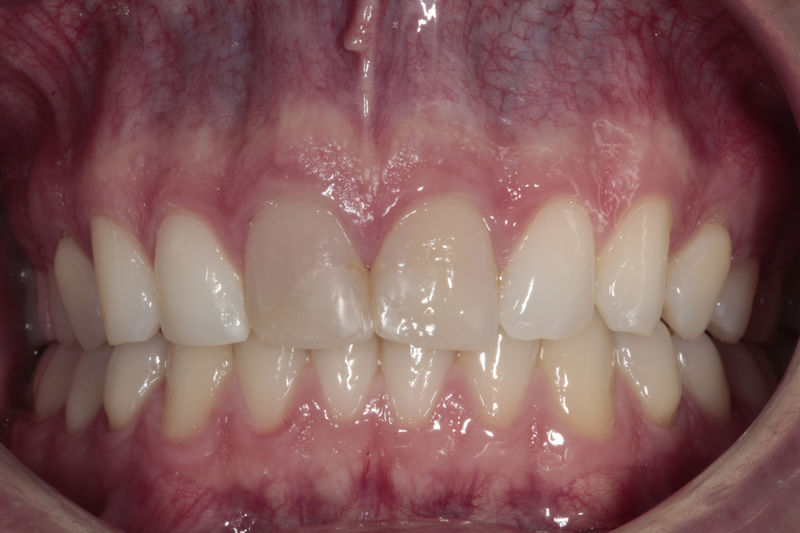

Amplia gama de tratamientos para mejorar la apariencia de la sonrisa, corrigiendo el color, la forma, el tamaño, la alineación y la posición de los dientes. Los procedimientos más comunes y solicitados incluyen el blanqueamiento dental, las carillas y coronas, así como las resinas.

Son restauraciones que cubren toda la cara frontal del diente, generalmente empleadas en el sector anterior y cuya finalidad es primariamente estética.

Ortodoncia y coronas.